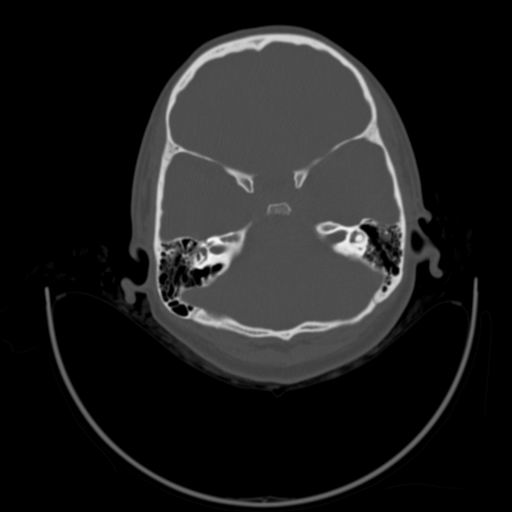

以下是引用随光逐影在2009-3-14 7:58:00的发言:[br]双耳——颞骨ct轴位平扫未见明确异常。